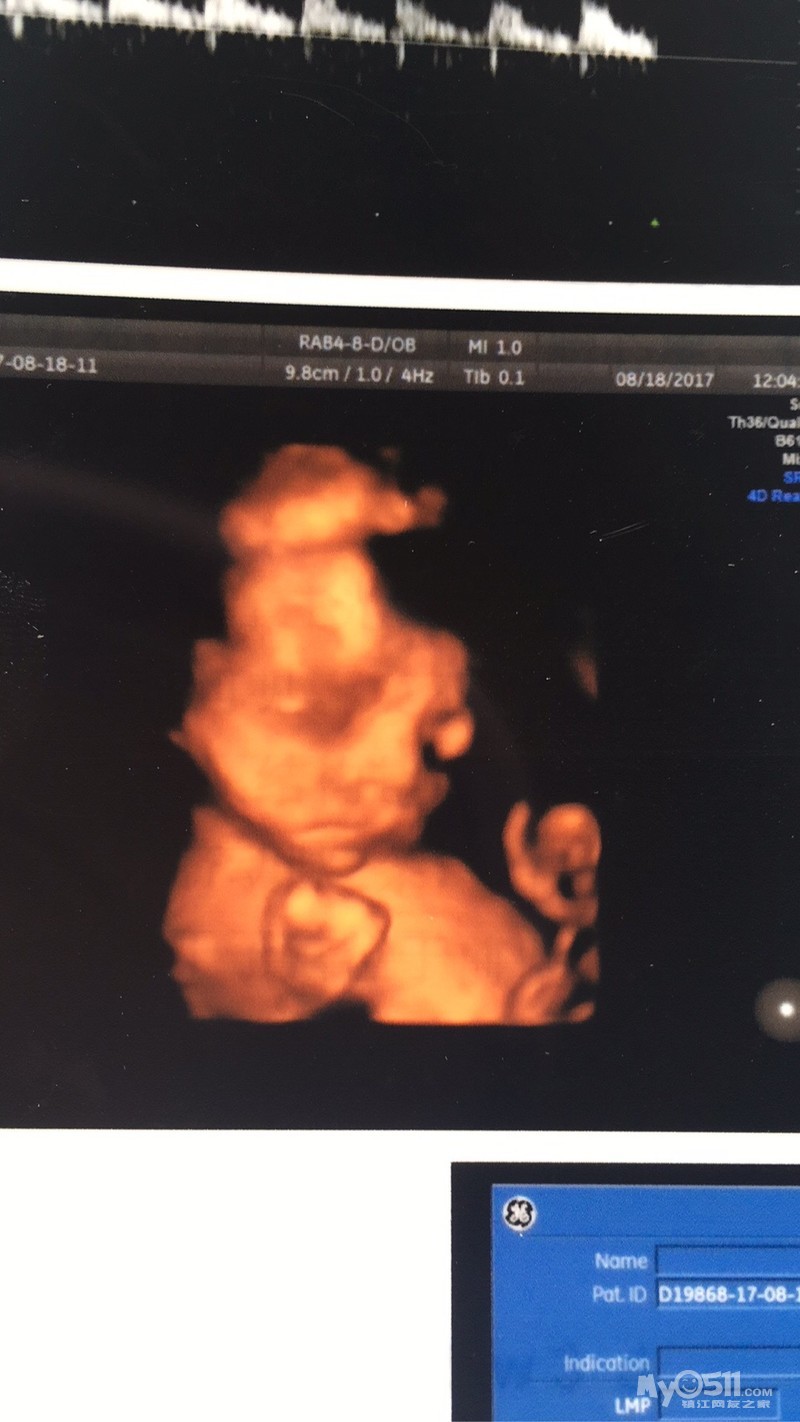

还记得三月底,发现试纸隐约两道杠,激动的一夜没睡着。备孕一年,终于盼来了鸡宝宝。

孕前期,老流血,在家躺了几个月,整个人都躺的不好了,一直保胎到19周,后来去医院做唐筛时低风险通过,开心的都要哭了。盼了一个月,终于盼来了四维,

恭喜恭喜 四维的小脸萌萌哒

照片是握着个小拳头嘛,好可爱

四维图 好大 好清楚啊

四维过了,糖筛过了